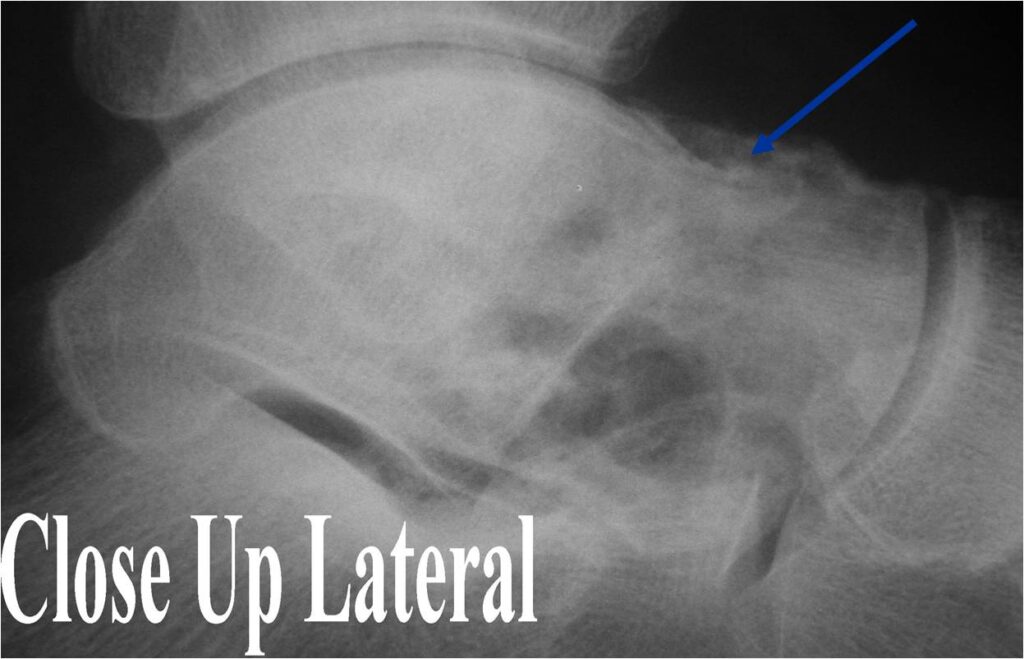

Radiographic Presentation

- Presents as a highly defined/well circumscribed geographic oval/round lytic defect

- Surrounded by rim of sclerotic bone

- Usually in epiphyseal region

- (Plain x-ray appearance)

- Geographic lytic lesion IA/IB margin of sclerosis

- Usually Eccentric more often than Central in the bone

- Rarely expansile (rarely penetrates the cortex)

- (MRI appearance)

- Geographic, well circumscribed lesion in the epiphysis

- Intermediate Signal on T1

- High signal on T2 mixed with low signal areas (low signal areas proposed to be secondary to lysosomal content of highly cellular areas)

- Fluid/Fluid levels demonstrated in tumors that have undergone ABC change (aneurysmal bone cyst change)

- Extensive Surrounding edema is common

- Joint effusion in 30-50% of cases

- (CT appearance)

- Most useful for detecting subtle mineralization not apparent on X-rays

- Useful for identifying intact periosteum around any expansile soft tissue component

- surrounding thin reactive shell of bone/mineralization (Egg Shell Rim of Calcification)

- helps place the tumor in a benign category

- helps evaluate:

- bony quality

- extent of bone and cortical destruction

- whether the subchondral plate of bone adjacent to the articular cartilage has been destroyed or is intact